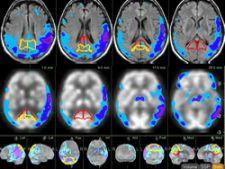

MIMneuro provides fully automated quantitative analysis of neurological disorders including Alzheimer’s Disease and other dementias. MIMneuro performs sophisticated deformable registrations, facilitating comparisons to a database of age-appropriate normals.1 A comprehensive 3D Anatomical Brain Atlas is included to allow easy localization of structures of interest.

The MIMneuro Epilepsy Workflow quickly performs ictal-interictal SPECT subtractions and fusion with MR to localize epileptic foci.